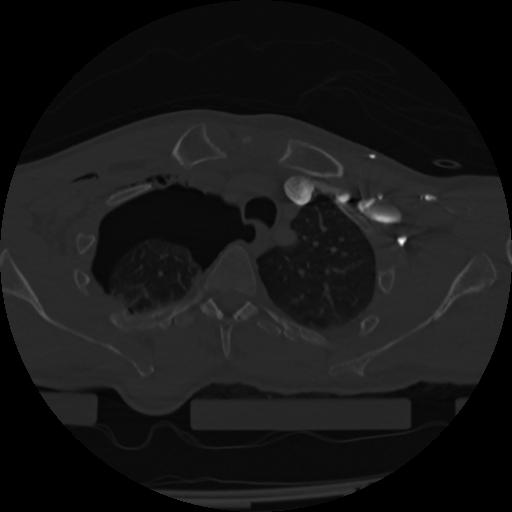

22 ANGIO,CE,Vol,0.5,ANGIO,,